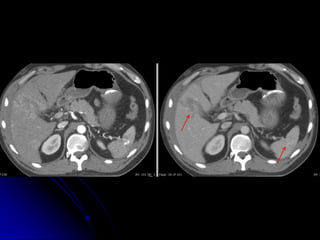

INCIDENTAL

FINDINGS &

COMORBIDITIES

COMMUNICATION